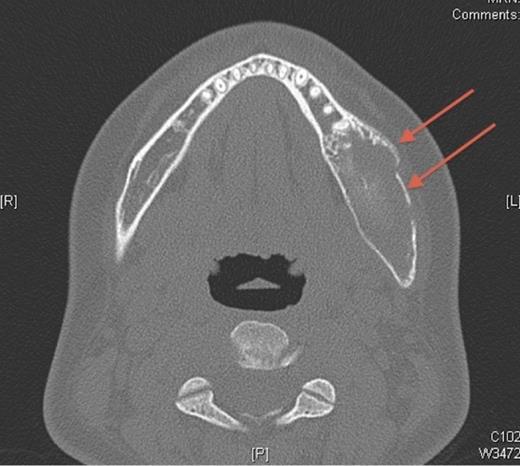

Pre-operative axial CT showing the lesion in the left side of the mandible (denoted by arrows).